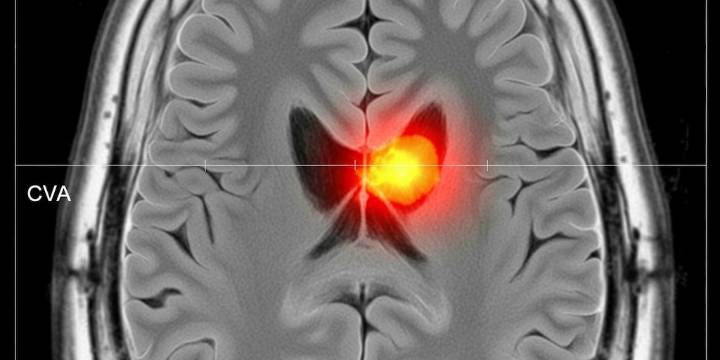

Los accidentes cerebrovasculares se mantienen como una de las principales causas de discapacidad y mortalidad a nivel mundial, una situación cuya gravedad ha cobrado mayor notoriedad tras los casos recientes de Donald Glover , Hailey Bieber y Jamie Foxx .

El Dr. Gurutz Linazasoro , en entrevista con Hello Magazine , definió el accidente cerebrovascular (ictus) como un evento en